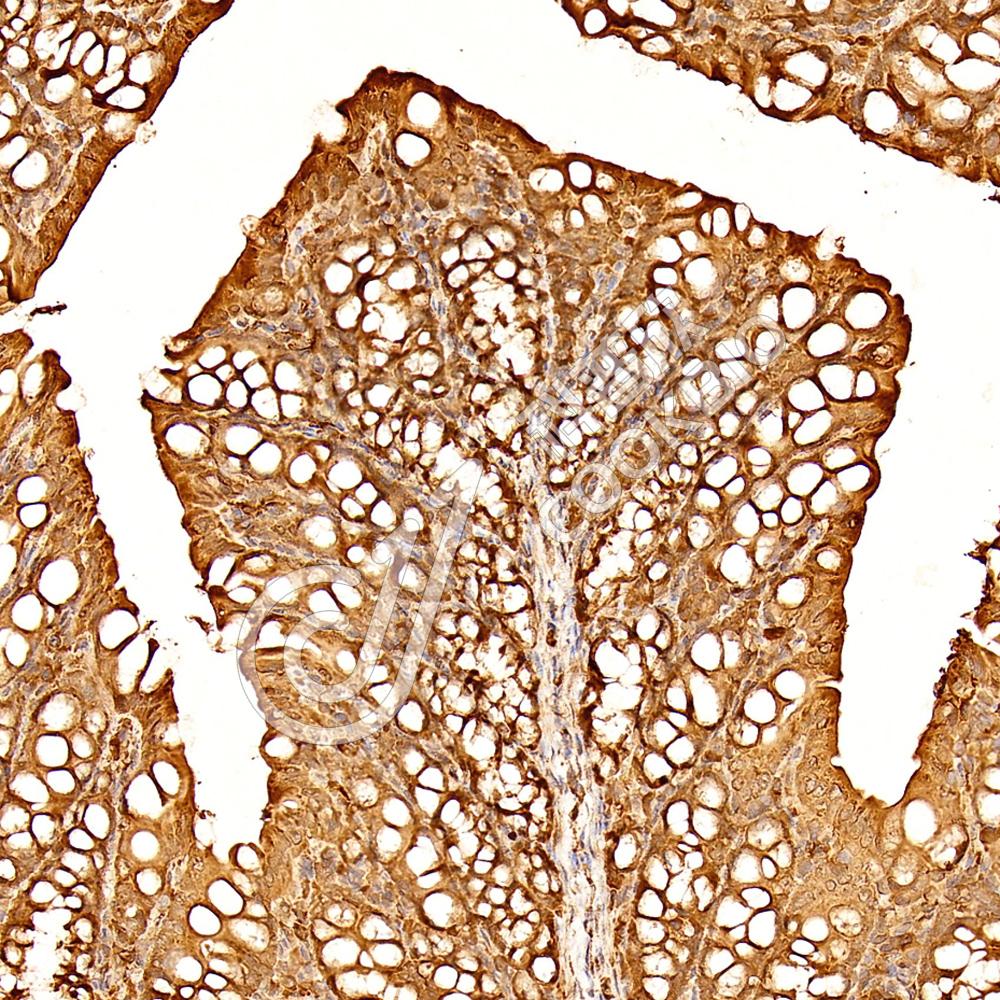

IHC检测EI2BL/MRI1蛋白(货号 K1344517).

样品: 小鼠结肠, 4%多聚甲醛 (货号KSG1101) 固定12-24小时.

抗原修复: 柠檬酸抗原修复液(干粉, pH 6.0) (KSG1201), 98℃, 20分钟.

—抗: 1: 1000稀释, 4℃ 孵育过夜.

二抗: S-vision免疫组化多聚二抗(山羊抗兔),即用型 (货号KB3906), 室温孵育20分钟.